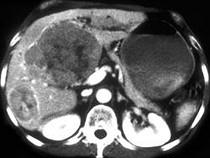

女,67岁,右上腹疼痛,消瘦四月余,CT检查如图,最可能的诊断是()A.肝血管瘤B.肝脓肿C.肝癌D.肝转移瘤E.肝囊肿

问题 女,67岁,右上腹疼痛,消瘦四月余,CT检查如图,最可能的诊断是()

选项 A.肝血管瘤 B.肝脓肿 C.肝癌 D.肝转移瘤 E.肝囊肿

答案 C